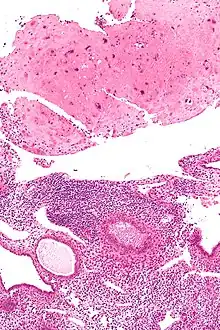

| Micrograph of a placental site nodule (top of image). H&E stain. |

A placental site nodule (PSN) is benign remnant from a previous pregnancy.[1]

PSNs are intermediate trophoblastic remnants.

Typically, they consist of pink (hyaline) material using the standard stain and contain few cells. Bizarre multinucleated cells may be present; however, there is no mitotic activity. The differential diagnosis includes (cervical) squamous cell carcinoma, gestational trophoblastic disease, and exaggerated placental site.